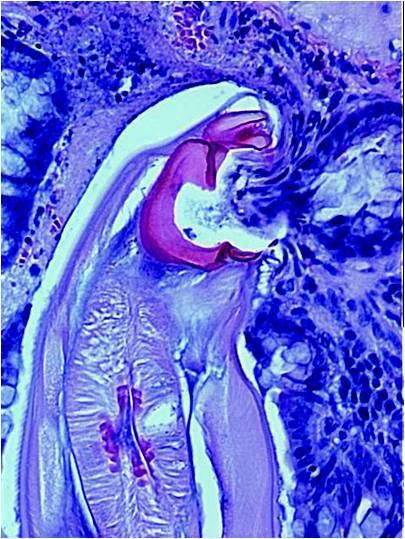

In this study, the team looked at whether women of child-bearing age -- who may be especially vulnerable to hookworm -- should be included in mass drug treatment campaigns targeting the infections, which are acquired from contact with soil contaminated with human sewage. The worms feed on blood and cause chronic anemia.

Poor women of childbearing age are seen as particularly vulnerable due to the blood loss they already experience from menstruation and, if pregnant, from the demands of the fetus. Cappello and his research team at Yale has also linked hookworms to inflammation in the intestines and interference with natural digestive enzymes which may contribute to malnutrition and lead to other maladies, said Cappello.